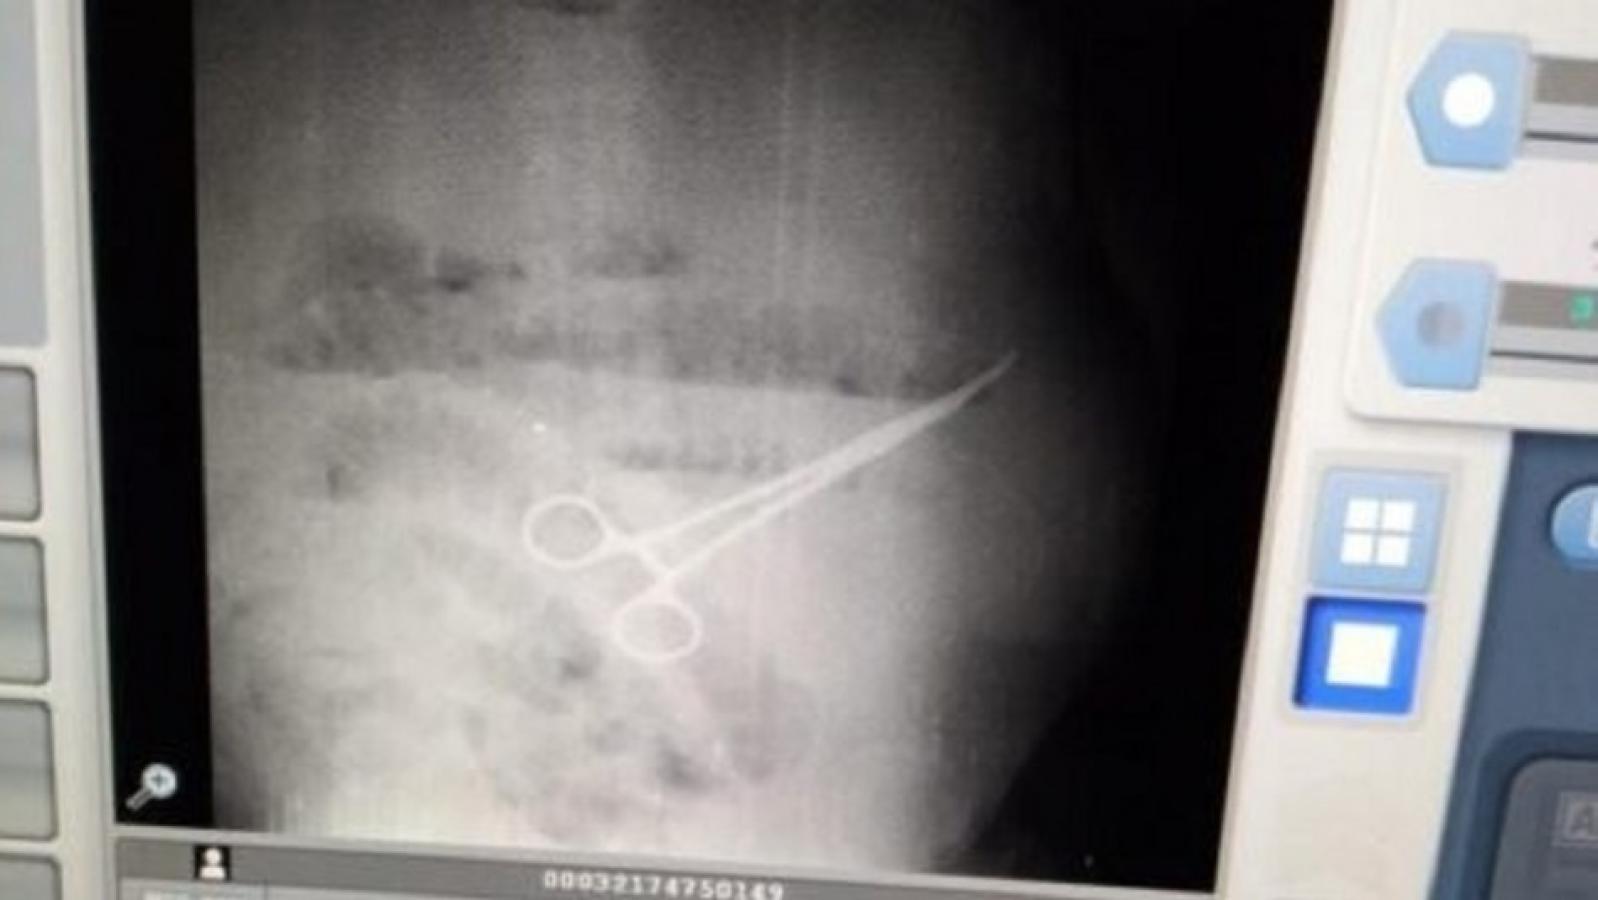

Ante esto, los profesionales decidieron realizar una prueba de rayos X, en el que se reveló el objeto que tenía en su estómago: una tijera quirúrgica.